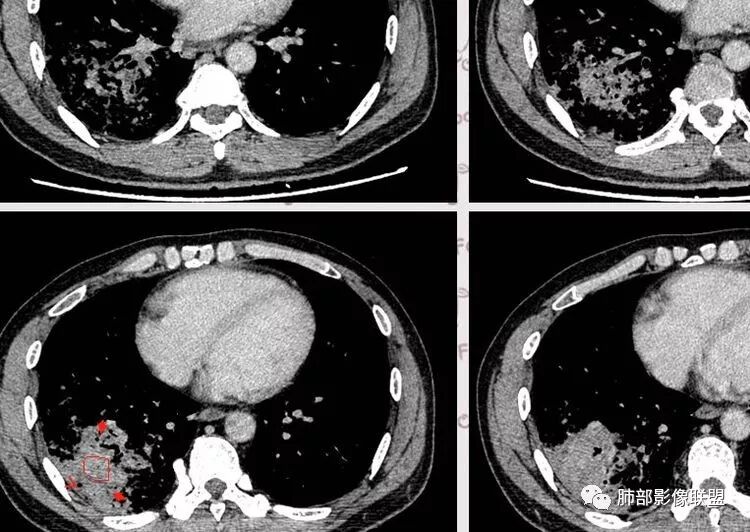

王秀仙东宁市第二人民医院影像科:晨读:右肺下叶实变及磨玻璃影,边缘有收缩有膨隆,部分支气管进入扭曲扩张,磨玻璃影边缘清晰,实变影明显强化,内可见血管造影征,纵膈及肺门淋巴结肿大并强化,考虑粘液腺癌。

登封市三康医院(刘权威):右下肺肺不张,磨玻璃影,边缘清楚,空气支气管征,增强有强化,纵膈及右肺门淋巴结肿大并强化,考虑恶性肿瘤,粘液腺癌可能。

但是问题来了:淋巴结

南边:

右肺门区淋巴结增大,融合,密度均匀,均匀强化

符合这个特点的:结核?淋巴瘤?转移瘤?

淋巴结我觉得目前的特点:淋巴瘤?结核?

复查胸部CT视频显示肺部病灶明显吸收,淋巴结较前缩小。

患者在本院做了支气管镜,报告是有新生物,取了活检就转院了。病理结果是后来出来的。去肿瘤医院再做支气管镜,病理还是炎症。抗炎治疗(电话追问患者家属,具体不详)一个月后复查,右下肺病变基本吸收,肺门肿块明显变小;纵隔淋巴结基本都没了或者明显变小了

我一直以为是二元的,我觉得特别淋巴结里面又有钙化灶,我的想法肺部就是炎性病变,因为很典型的分布符合气道来源炎性病变,但是淋巴结是独立出来的,里面有钙化灶怀疑结核可能。